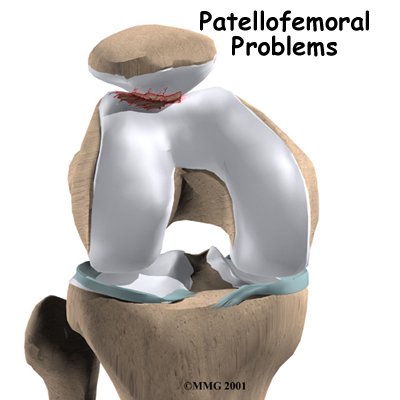

The patella, or kneecap, can be a source of knee pain when it fails to function properly. Alignment or overuse problems of the patella can lead to wear and tear of the cartilage behind the patella. This produces pain, weakness, and swelling of the knee joint. Several different problems can affect the patella and the groove it slides through in the knee joint. These problems can affect people of all ages.

The underside of the patella is covered with articular cartilage, the smooth, slippery covering found on joint surfaces. This covering helps the patella glide (or track) in a special groove made by the thighbone, or femur. This groove is called the femoral groove.

Problems commonly develop when the patella suffers wear and tear. The underlying cartilage begins to degenerate, a condition sometimes referred to as chondromalacia patella. Wear and tear can develop for several reasons. Degeneration may develop as part of the aging process, like putting a lot of miles on a car. The patellofemoral joint is usually affected as part of osteoarthritis of the knee.

Finally, anatomic variations in the bones of the knee can occur such that one side of the femoral groove is smaller than normal. This creates a situation where the groove is too shallow, usually on the outside part of the knee. People who have a shallow groove sometimes have their patella slip sideways out of the groove, causing a patellar disclocation. This is not only painful when it occurs, but it can damage the articular cartilage underneath the patella. If this occurs repeatedly, degeneration of the patellofemoral joint occurs fairly rapidly.

Finally, anatomic variations in the bones of the knee can occur such that one side of the femoral groove is smaller than normal. This creates a situation where the groove is too shallow, usually on the outside part of the knee. People who have a shallow groove sometimes have their patella slip sideways out of the groove, causing a patellar disclocation. This is not only painful when it occurs, but it can damage the articular cartilage underneath the patella. If this occurs repeatedly, degeneration of the patellofemoral joint occurs fairly rapidly.